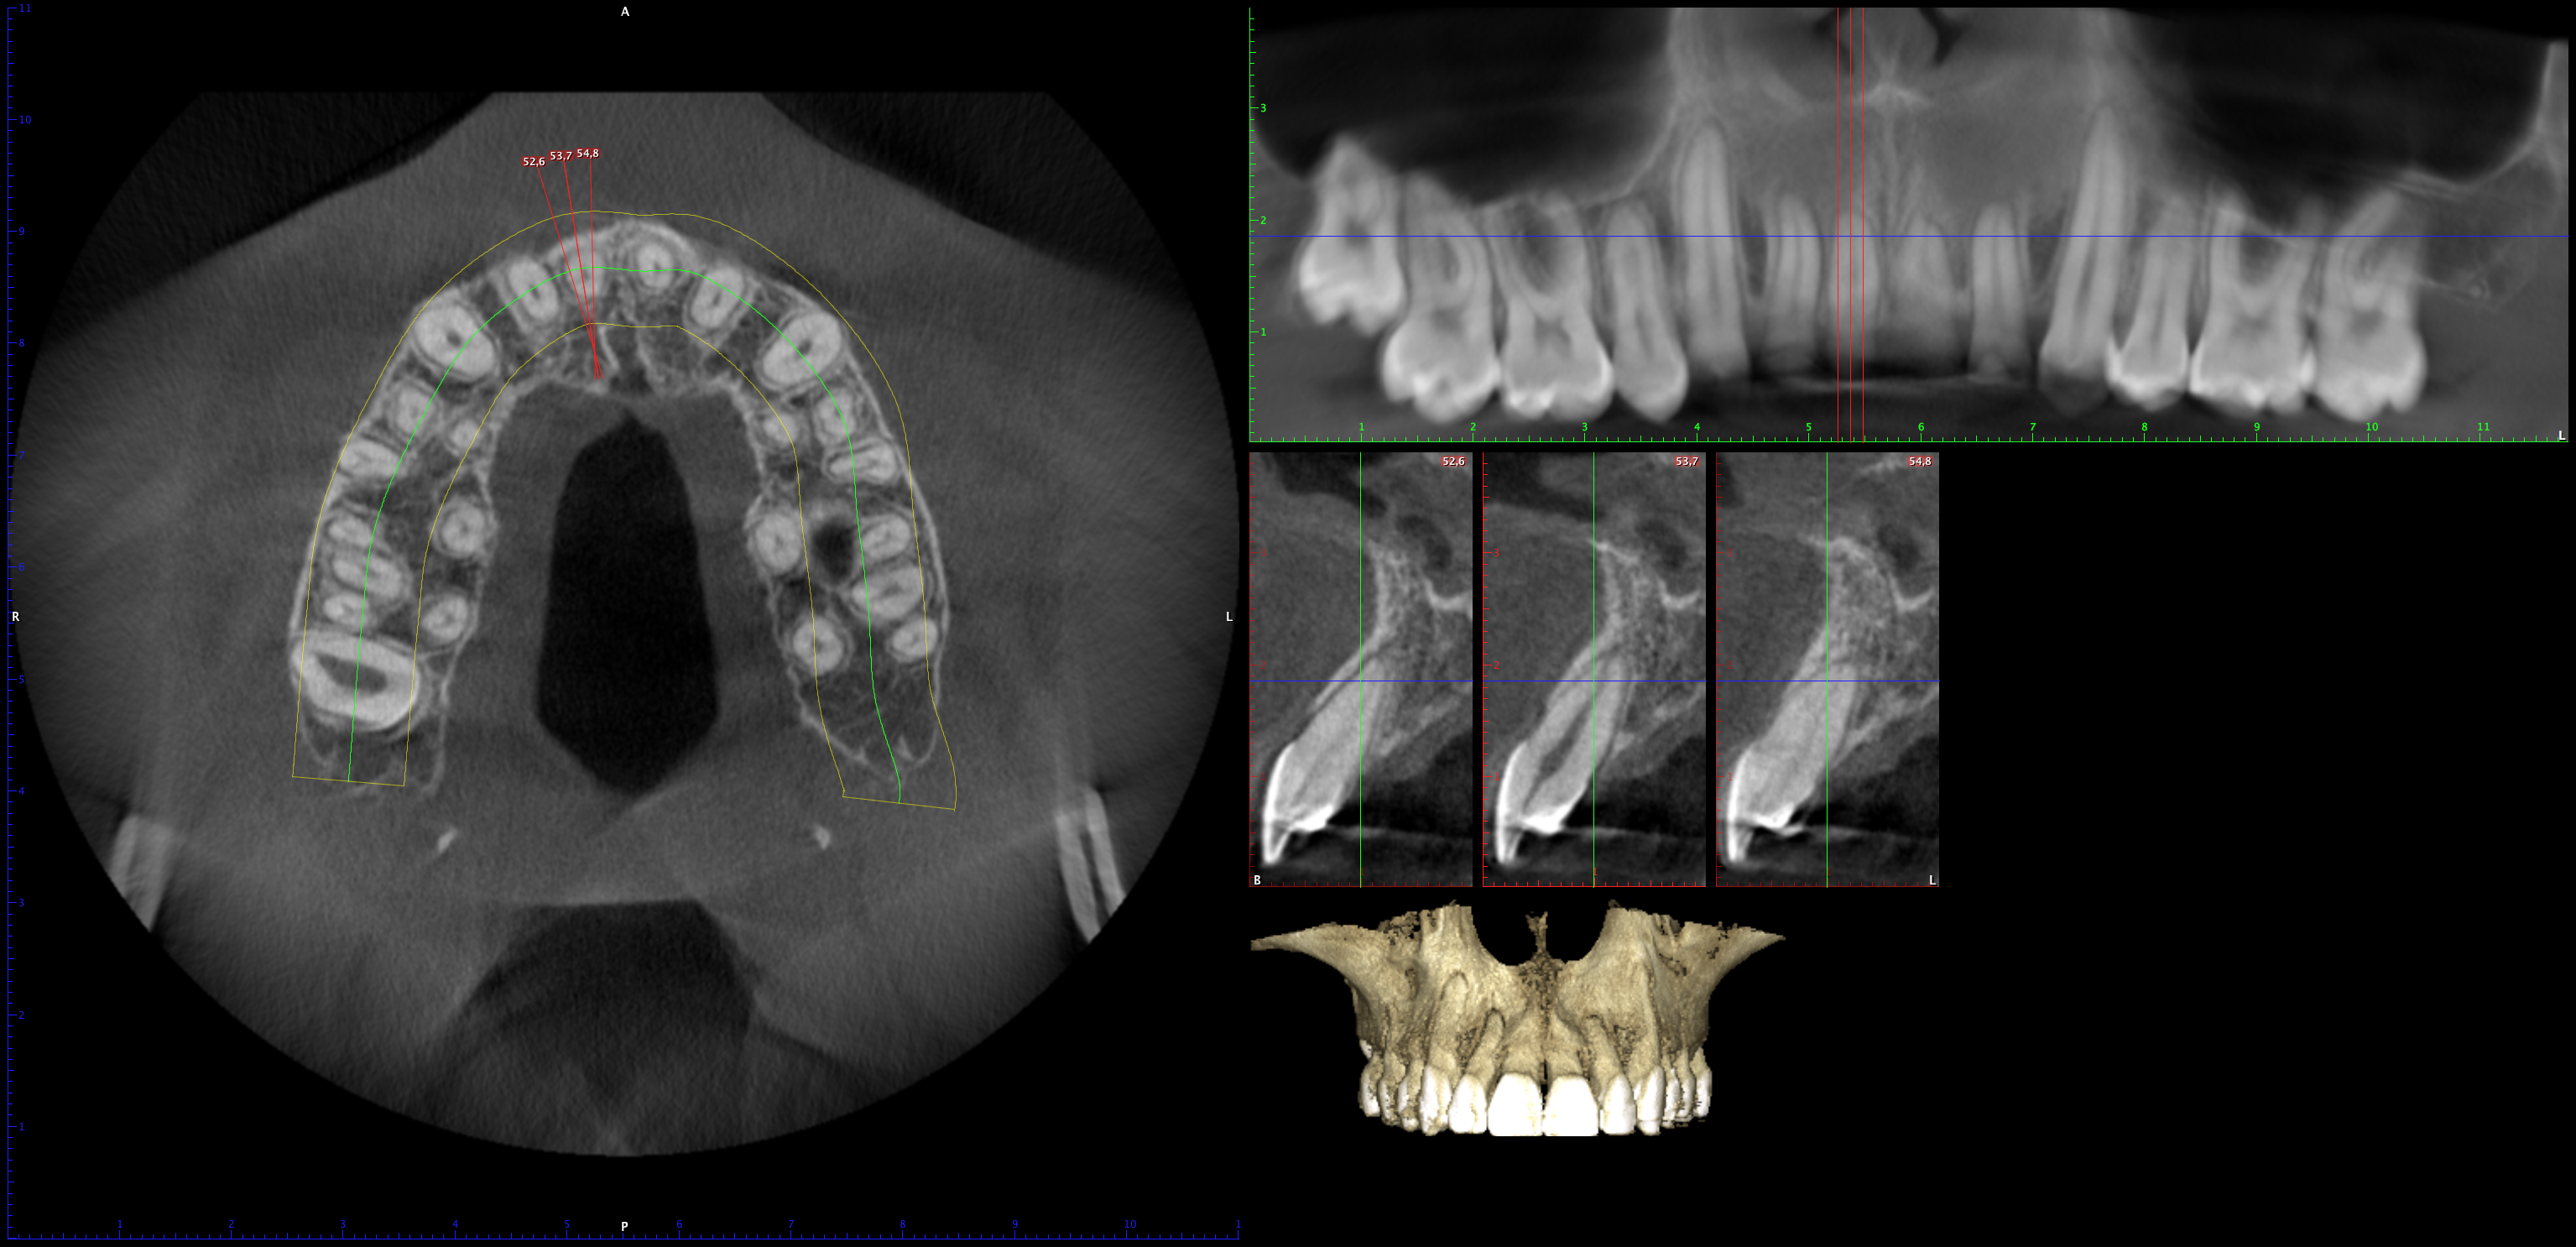

En PROTAC conseguimos una combinación ideal de calidad de imagen y usabilidad de alto nivel, ya que disponemos de una unidad CBCT(Cone Beam Computed Tomography) de última generación que supone un extraordinario avance en la evolución del procesamiento de imágenes de haz cónico, obteniendo una calidad de imagen optimizada, reduciendo los artefactos y garantizando imágenes de mayor contraste, para conseguir así satisfacer las necesidades del exigente procesamiento de imágenes maxilofaciales en todos los entornos clínicos. Nuestro innovador software Planmeca Romexis® ofrece herramientas especialmente diseñadas para especialistas en implantología, endodoncia, periodoncia, prostodoncia, ortodoncia, cirugía maxilofacial y otorrinolaringología.

Nuestra unidad de escáner y radiografía dental y nuestro software de procesamiento de imágenes brinda una combinación innovadora de imágenes 2D y 3D que le ofrecen una visión más completa para conocer con mayor exactitud las necesidades de sus pacientes.

Unidad CBCT de última generación con una calidad de imagen optimizada.

Software con herramientas especializadas para implantología, endodoncia, periodoncia, prostodoncia, ortodoncia, cirugía maxilofacial y otorrinolaringología.

Imágenes 2D y 3D más completas para conocer con mayor exactitud las necesidades de sus pacientes.